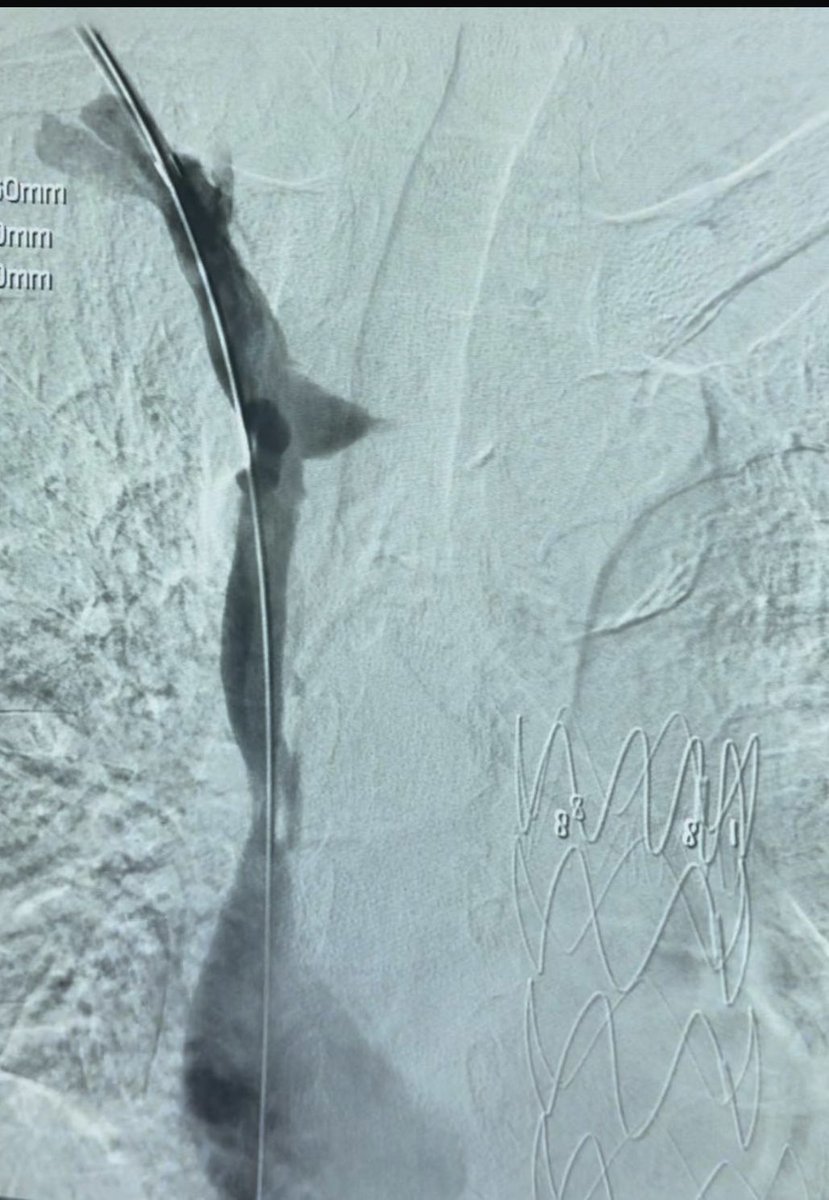

مريض يعاني من انسداد كامل في الوريد الأجوف العلوي. بالأشعة التداخلية أُعيد فتح الوريد وتدفق الدم من جديد، غالبًا بسبب قساطر قديمة. حياة أفضل للمريض

abeerfd's tweet image. مريض يعاني من انسداد كامل في الوريد الأجوف العلوي.

بالأشعة التداخلية أُعيد فتح الوريد وتدفق الدم من جديد، غالبًا بسبب قساطر قديمة.

حياة أفضل للمريض